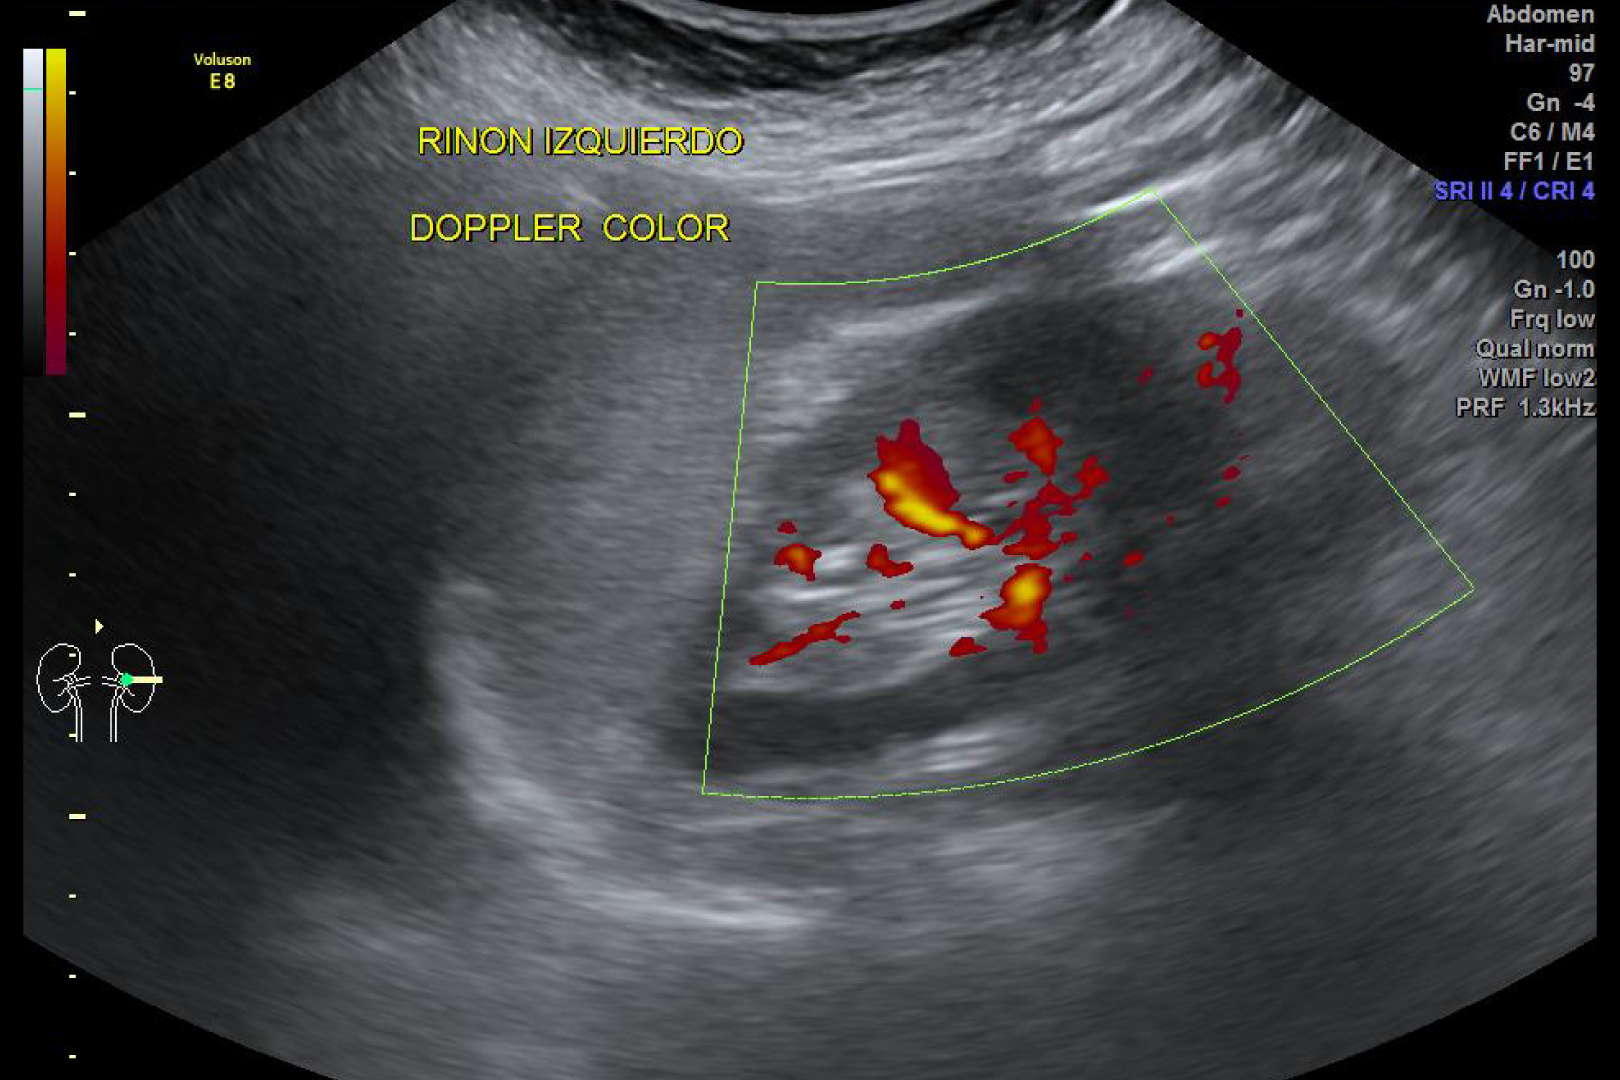

HD Live quinta dimensión, Imágenes de volumen con profundidad y claridad, que aportan un realismo anatómico para un mejor diagnóstico.